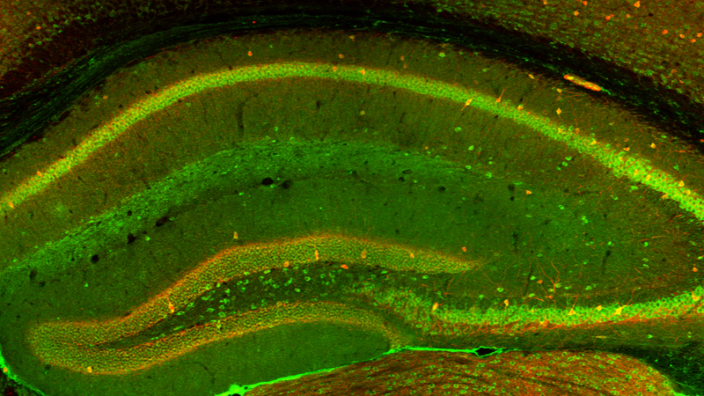

The Hedgehog Protein Reduces Microglial Inflammation in Mice

Researchers, publishing in the journal Aging, have discovered that a protein called hedgehog alleviates the tissue-specific, age-related inflammation of the microglia, the maintenance cells of the brain.

To begin this research, the team first performed a gene expression analysis on four different types of murine macrophages: bone marrow-derived macrophages (BMDMs), peritoneal cavity macrophages, Kupffer cells, and microglia. This analysis discovered which genes were expressed and repressed with aging, attempting to find out which age-related gene changes these cells had in common.

The answer was that there were remarkably few. Each of these four types of macrophages appears to genetically age in its own way; there were only seven genes whose expression changed with age between both sexes and among all macrophages. The researchers tested the pathways involved, with the idea that perhaps different genes were yielding similar results, and they found that even the fundamental pathways between these cell types were different.

Upon stress, old microglia secrete considerably more types of inflammatory factors than old macrophages of other types, and microglia have roughly 200 genes that are upregulated with age and 900 that are downregulated, which is considerably more than any of the other types. The researchers found that a full two-thirds of genes that are specific to microglia are affected by age. They hypothesized that this is due to the microglial environment rather than an inherent aging program.

A root cause and a potential treatment

One commonality between the macrophages was that genes that signal the hedgehog protein (Hh) were reduced. The researchers injected mice with vismodegib, a compound that inhibits Hh, and evaluated the macrophages. The results were striking; seven inflammatory factors dramatically increased, some by more than two orders of magnitude.

This led the researchers to question whether or not they could accomplish the reverse. They treated naturally aged mice with the Hh agonist Hh-Ag1.5. These results were also significant: mice treated with Hh-Ag1.5 were found to express the inflammatory factor tumor necrosis factor (Tnf) at levels nearly that of young mice.